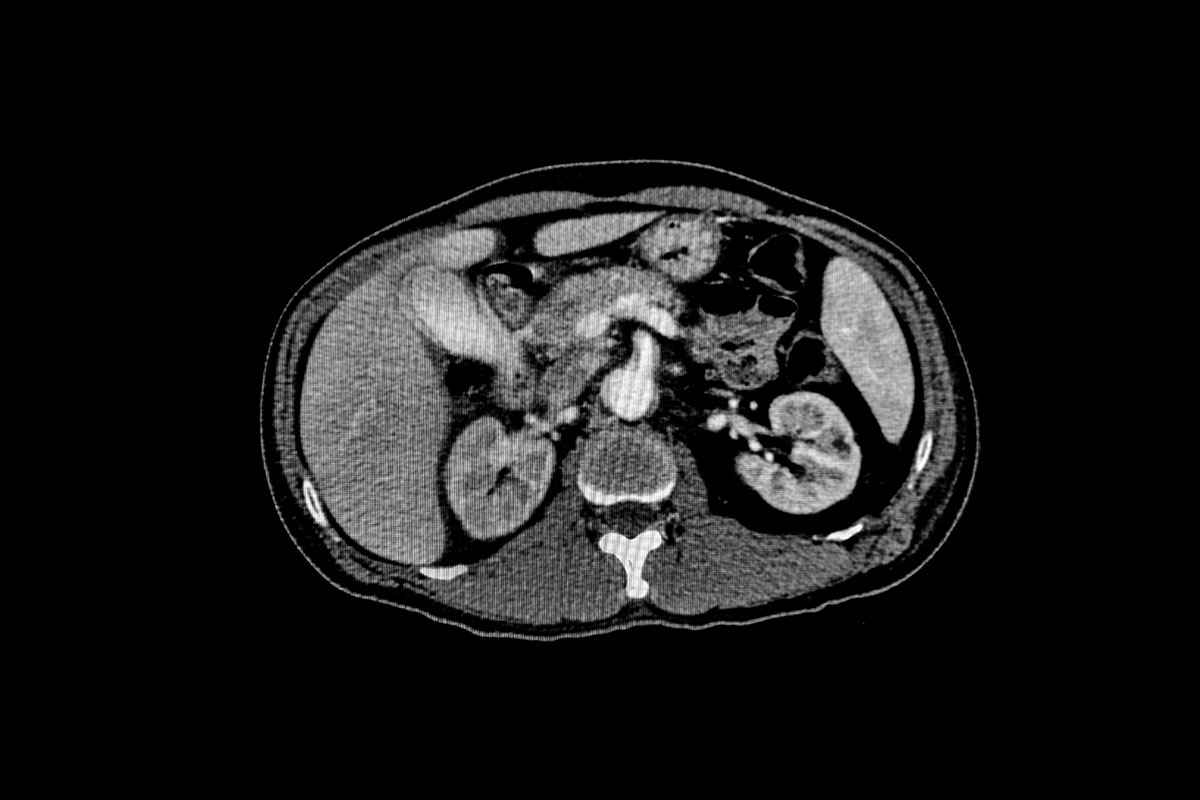

- コンピューター断層撮影 (CT): CT スキャンでは、回転 X 線装置を使用して、精巣とその周囲の領域の複数の断面画像を撮影します。